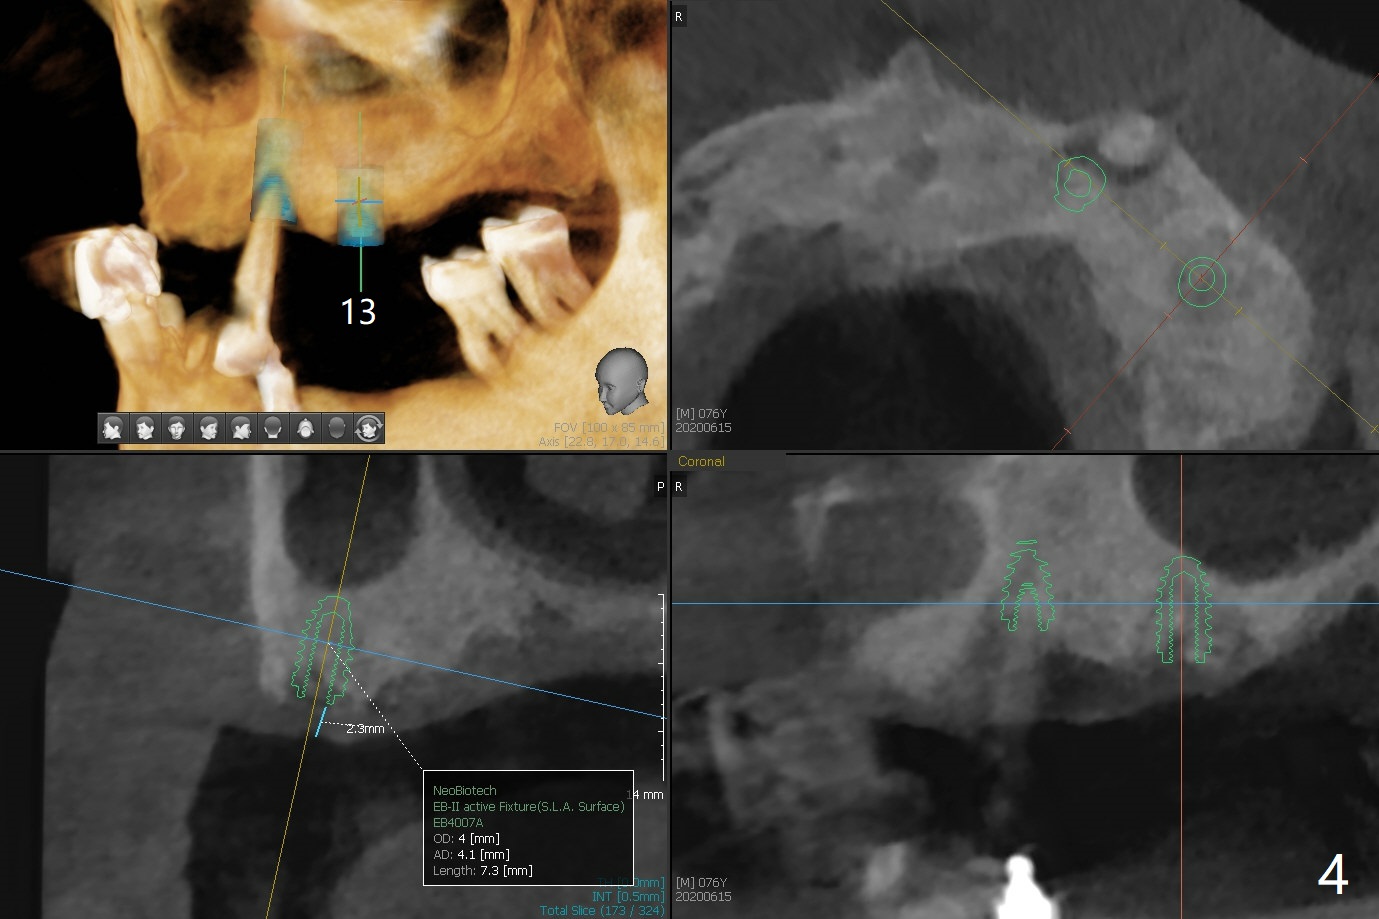

A 76-year-old man returns to clinic with chief complaint of loose top partial 2 years 3 months post #21 implant placement (Fig.1,2). The tooth #11 has mobility, while the socket of #13 heals and the tooth #1 is stable and functional (Fig.1). Two implants will be placed at #11 and 13 (Fig.3,4) with ball abutments (4 and 2 mm cuffs, respectively). Since the bone density is low at #13, bone expanders will be used as well as for sinus lift (implant 4x10 mm instead, PRF). Keep the tooth #11 as a denture one. Soft reline will be used to hold the abutments.